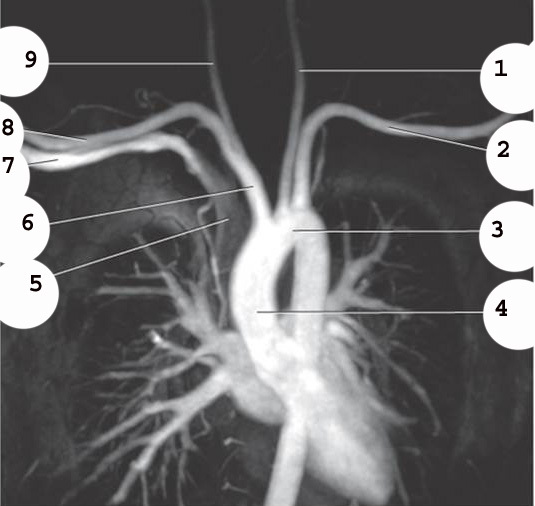

7

R subclavian vein

8

R subclavian Artery

9

R common carotid A